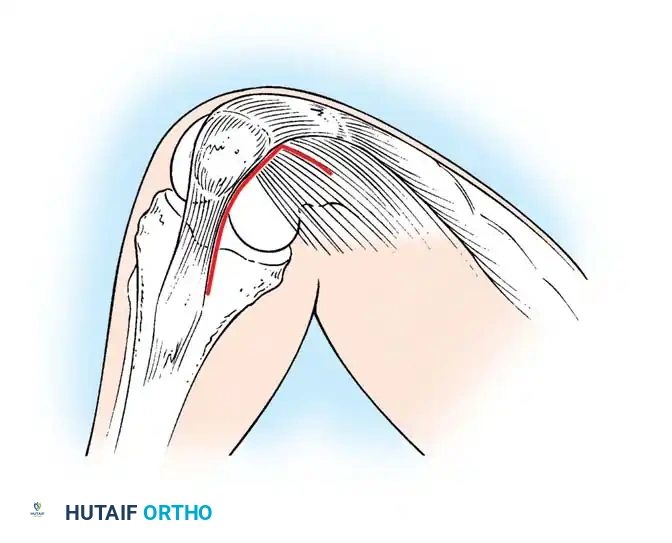

Surgical Approaches to the Knee

The most commonly used skin incision for primary TKA is an anterior midline incision. The choice of deep arthrotomy dictates the exposure of the joint and influences postoperative quadriceps recovery.